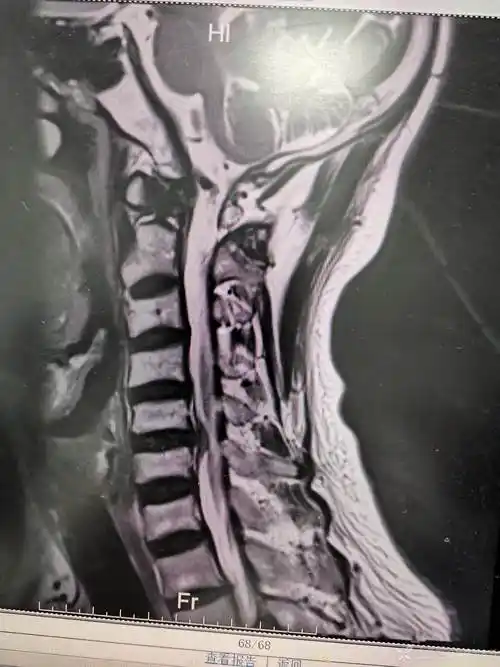

颈椎mri:颈5-6椎间盘突出,椎管狭窄,脊髓信号缺血改变.